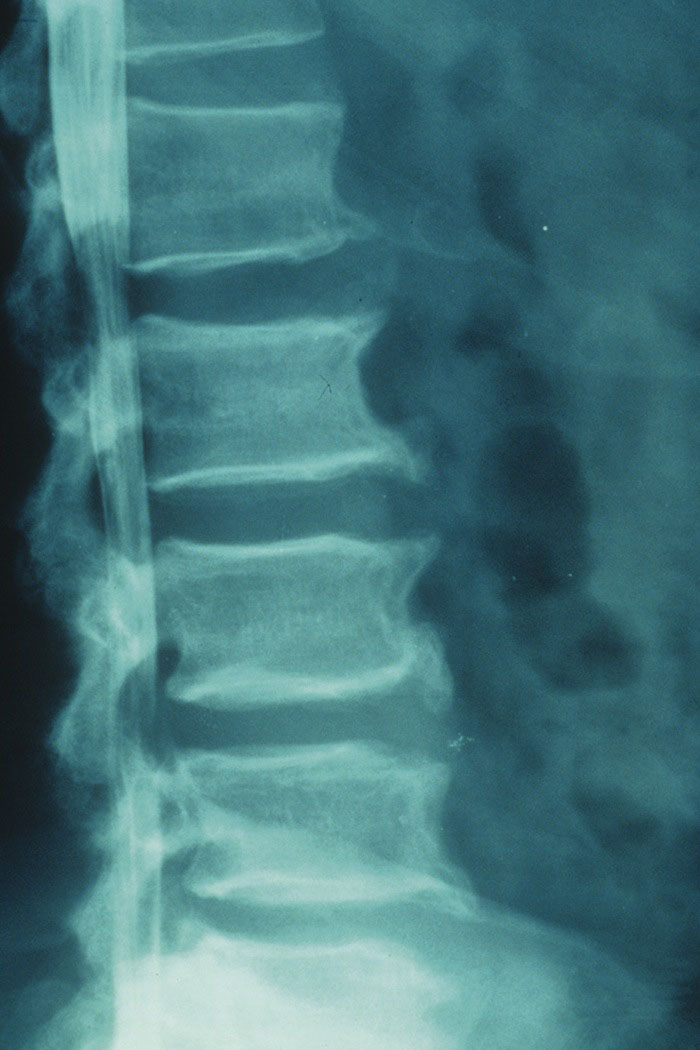

Avhandling. Kirurgi för lumbal spinal stenos (LSS) har ökat kraftigt. Det beror delvis på förbättrad diagnostik, men är framför allt ett uttryck för en förskjutning av ålderspyramiden med större andel äldre som har allt högre krav på fortsatt aktivitet och välmående. Målet med kirurgin är att avlasta nervstrukturerna i spinalkanalen genom att avlägsna de degenerativa förändringar som ger trängseln, så kallad dekompression.

För att minska risken för instabilitet efter operation har dekompressionen ofta kompletterats med en samtidig fusion (steloperation). Detta har varit särskilt vanligt vid preoperativ förekomst av kotglidning (degenerativ spondylolistes, DS). Fusion som tillägg till dekompressionen innebär dock en ökad risk för komplikationer och är mer resurskrävande. Dekompression kan göras på huvudsakligen två sätt: antingen centralt (laminektomi), då spinalutskott och ligament i medellinjen mellan kotorna avlägsnas, eller med separat åtkomst bilateralt (laminotomier) varvid dessa strukturer bevaras. Den senare tekniken är mer tekniskt krävande och behäftad med större risk för komplikationer med skador på nervstrukturer.